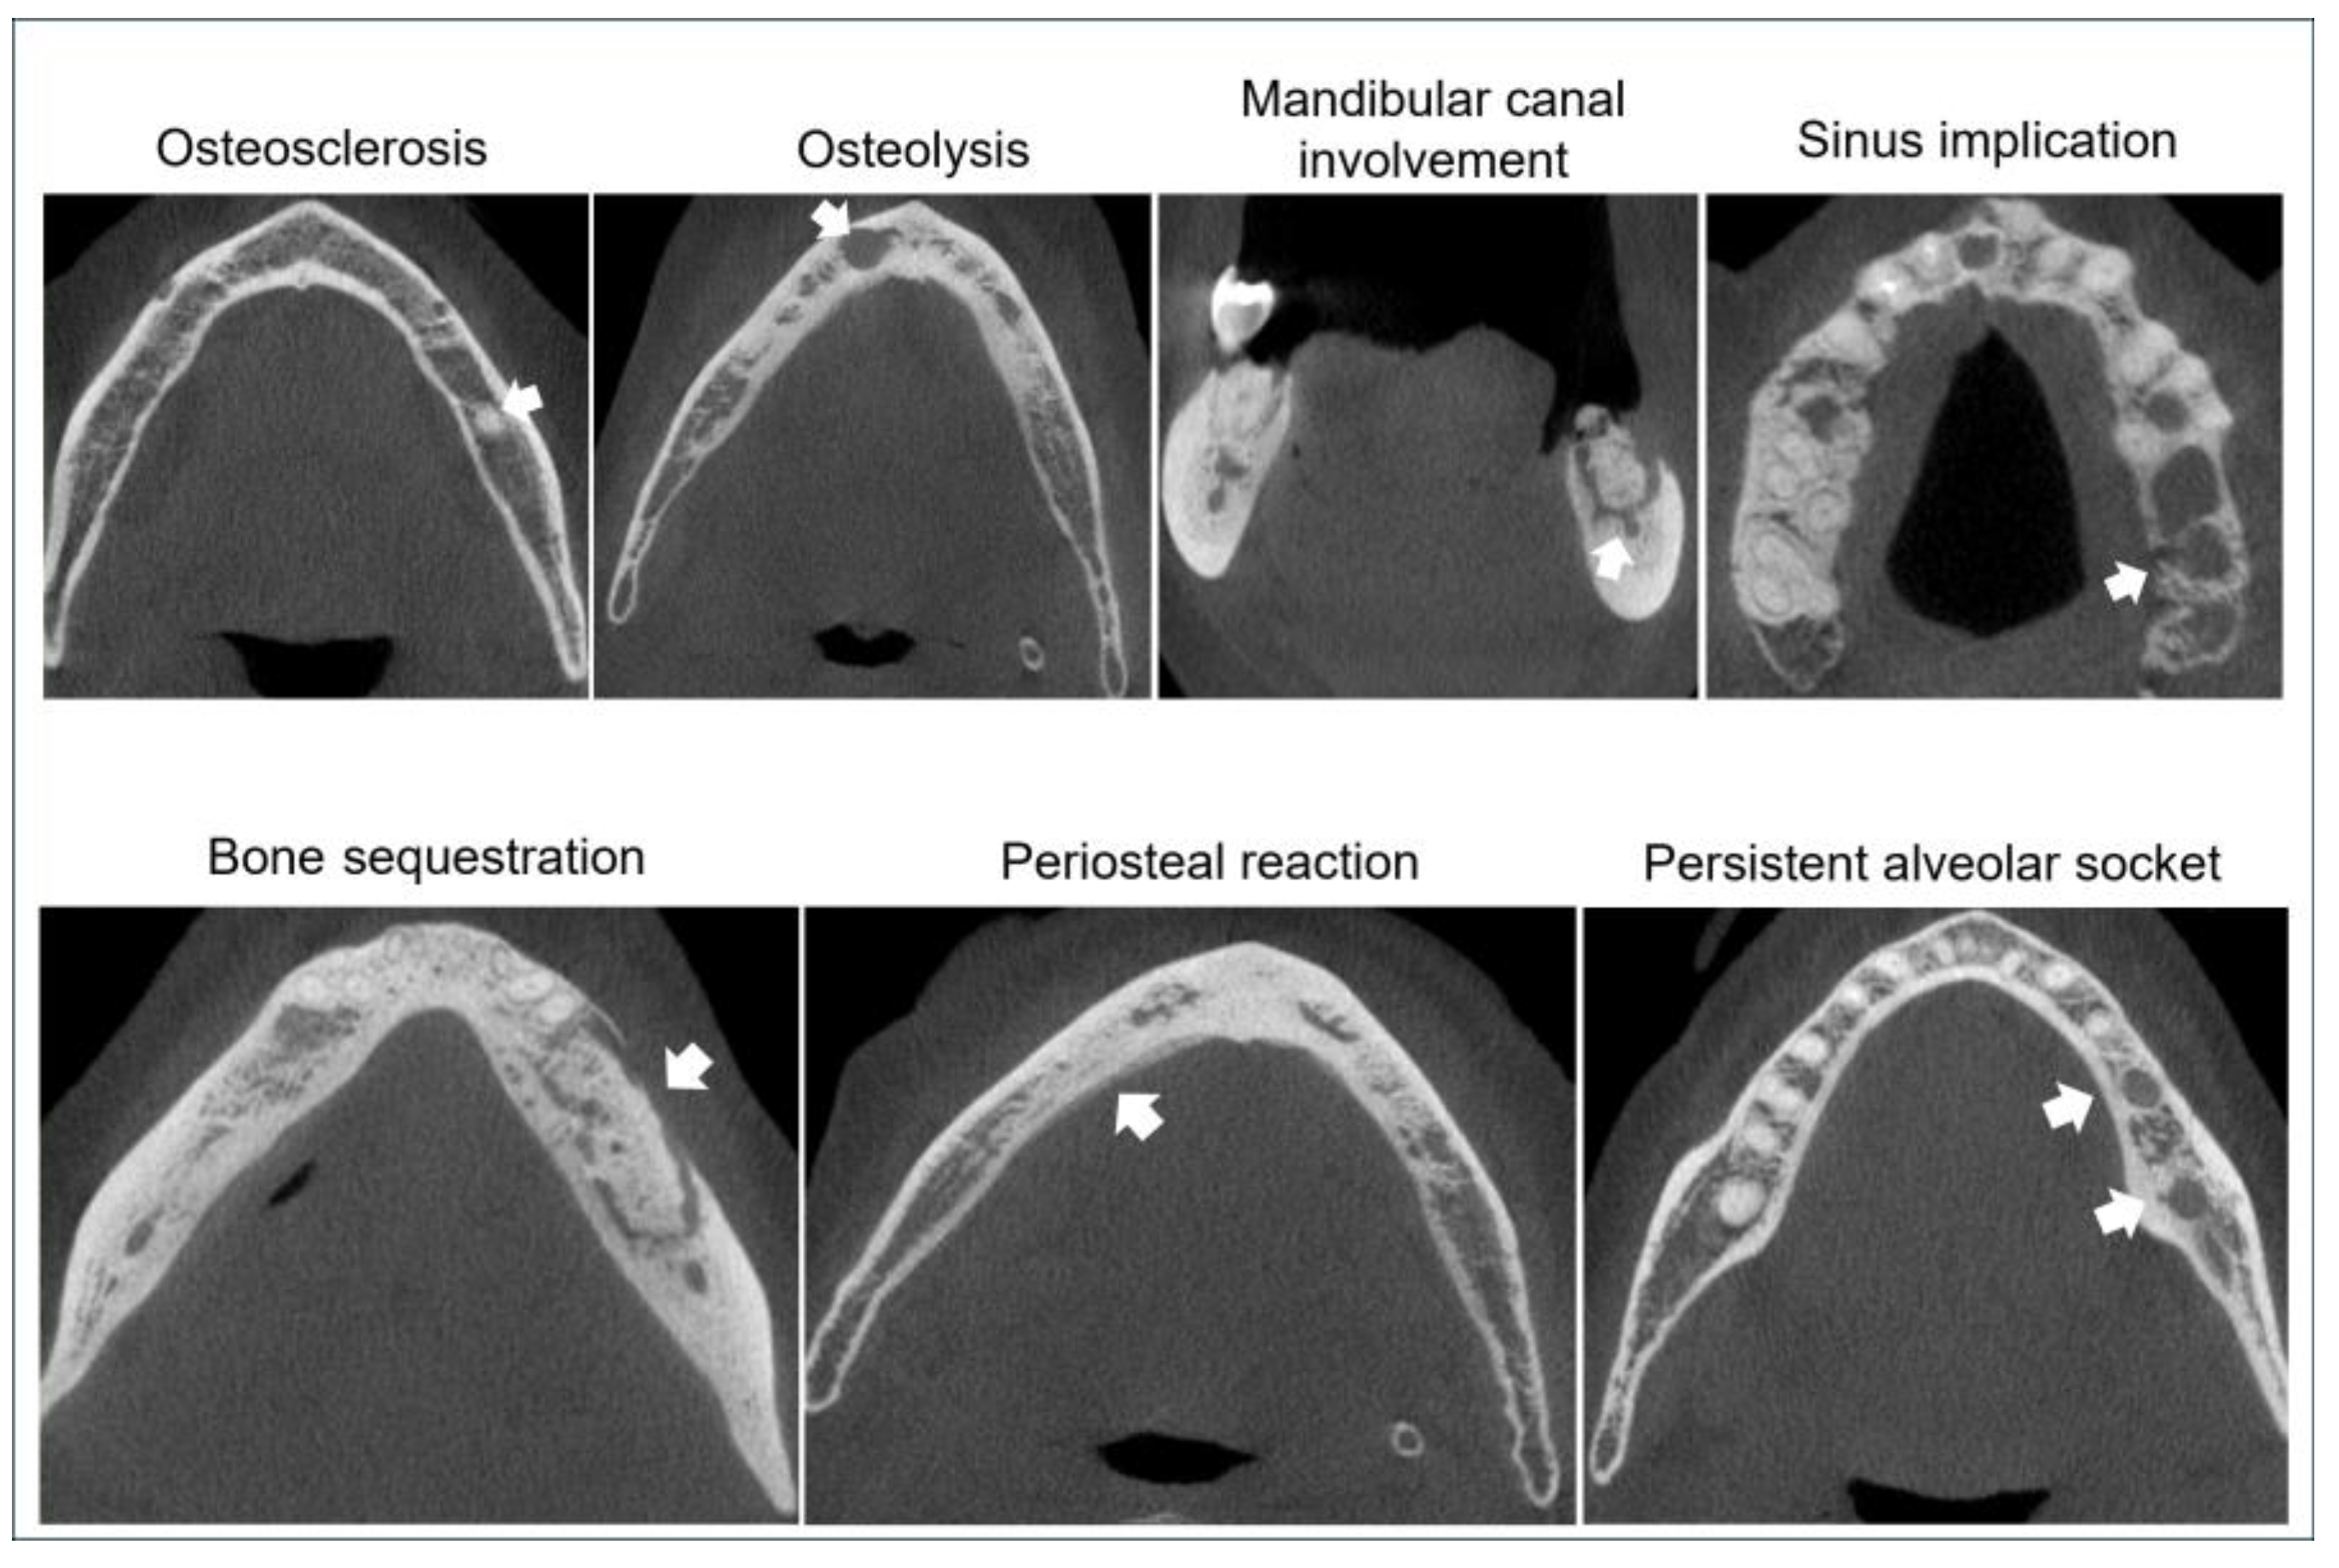

3.3.2. Bone Features on Cone Beam Computerized Tomography (CBCT)